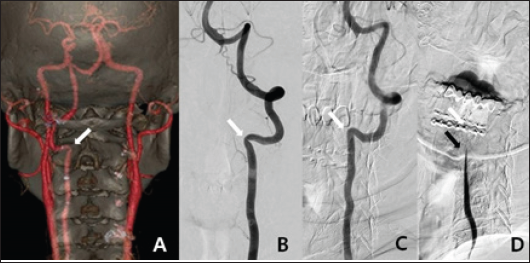

We scheduled brain and neck CTA, brain MRI, and three-position DSA. CTA revealed a hypoplastic right VA and left VA stenosis at the lateral curvature of the VA just below the C2 transverse foramen. Brain MRI revealed a tiny, acute ischemic infarction in the right cerebellum. DSA was performed in three positions (with the head neutral, 90° to the left, and 90° to the right). In the neutral position, left VA stenosis was observed just below the C2 transverse foramen, as on CTA. Notably, when the head was turned to the left, the VA stenotic lesion became wider than in the neutral position. When the head was turned to the right, the blood flow tapered at the C3-4 level and was totally occluded at the C2 level (Figure 2). Immediately after angiography with 90° to the right, the patient loosed consciousness and DSA was halt. As the right VA was hypoplastic and flow almost absent, the posterior circulation was highly dependent on the left VA. We concluded that the left VA became kinked just below the entry point of the C2 transverse foramen when the head was turned to the right. We decided to perform surgical decompression of the left VA.

Figure 2: A. The posteroanterior view of 3D-reconstruction CT angiography revealed left VA stenosis at the C2 transverse foramen (white arrow). B. The anteroposterior view of left VA angiography with the head in the neutral position revealed left VA stenosis at the C2 transverse foramen (white arrow). C. The lateral view of left VA angiography when the head was turned to the left revealed that the stenotic VA at C2 became wider than in the neutral position. D. The lateral view of left VA angiography when the head was turned to the right showed that blood flow decreased at the C3-4 level (black arrow) and stopped at the C2 level (white arrow).